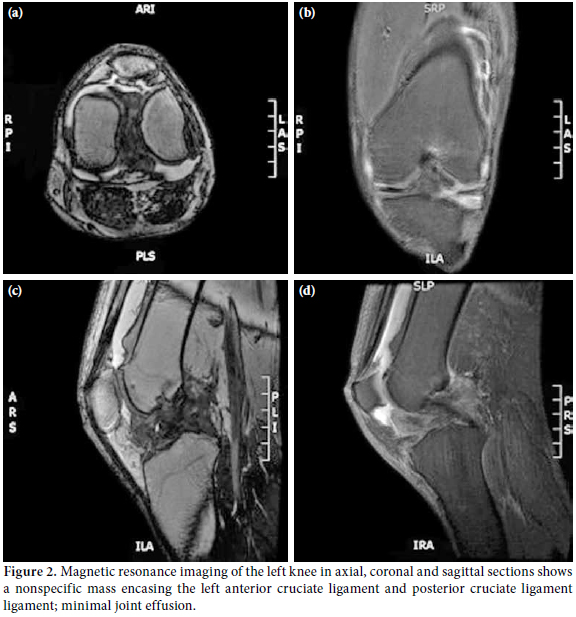

Laboratory investigations were unremarkable with the exception of elevated uric acid levels (611 umol/L). A plain radiograph of the left knee showed no abnormalities (Figure 1). Subsequently, magnetic resonance imaging (MRI) was ordered to determine the cause of the locked knee, and it showed minimal joint effusion with a hypointense soft tissue mass encasing the anterior cruciate ligament (ACL) and posterior cruciate ligament (PCL) measuring 5.7x1.5x2.2 cm. The MRI of the left knee in the axial, coronal, and sagittal sections revealed a nonspecific mass encasing the left ACL and PCL ligament with minimal joint effusion, which was suggestive of a synovial sarcoma of the left knee joint (Figure 2).